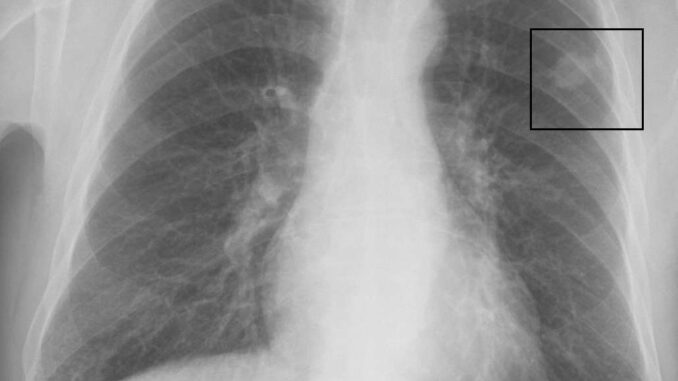

Das sind die erhöhten Sterbezahlen in Japan in Form von Übersterblichkeit.

Wir sehen, sie lagen deutlich über 25 % — ungefähr jetzt bei etwa 15 % — und waren seit einiger Zeit hoch. Es besteht etwas Unklarheit, ob sie 2020 schon höher waren oder nicht wenn ja, dann nur minimal. Aber als das Impfprogramm stärker wurde — 2021, 2022, 2023 und hinein in 2024 — stiegen die Sterberaten deutlich. Das sind Gesamtsterbefälle, nicht spezifisch Krebs, daher werde ich euch gleich die differenzierten Aufschlüsselungen geben.